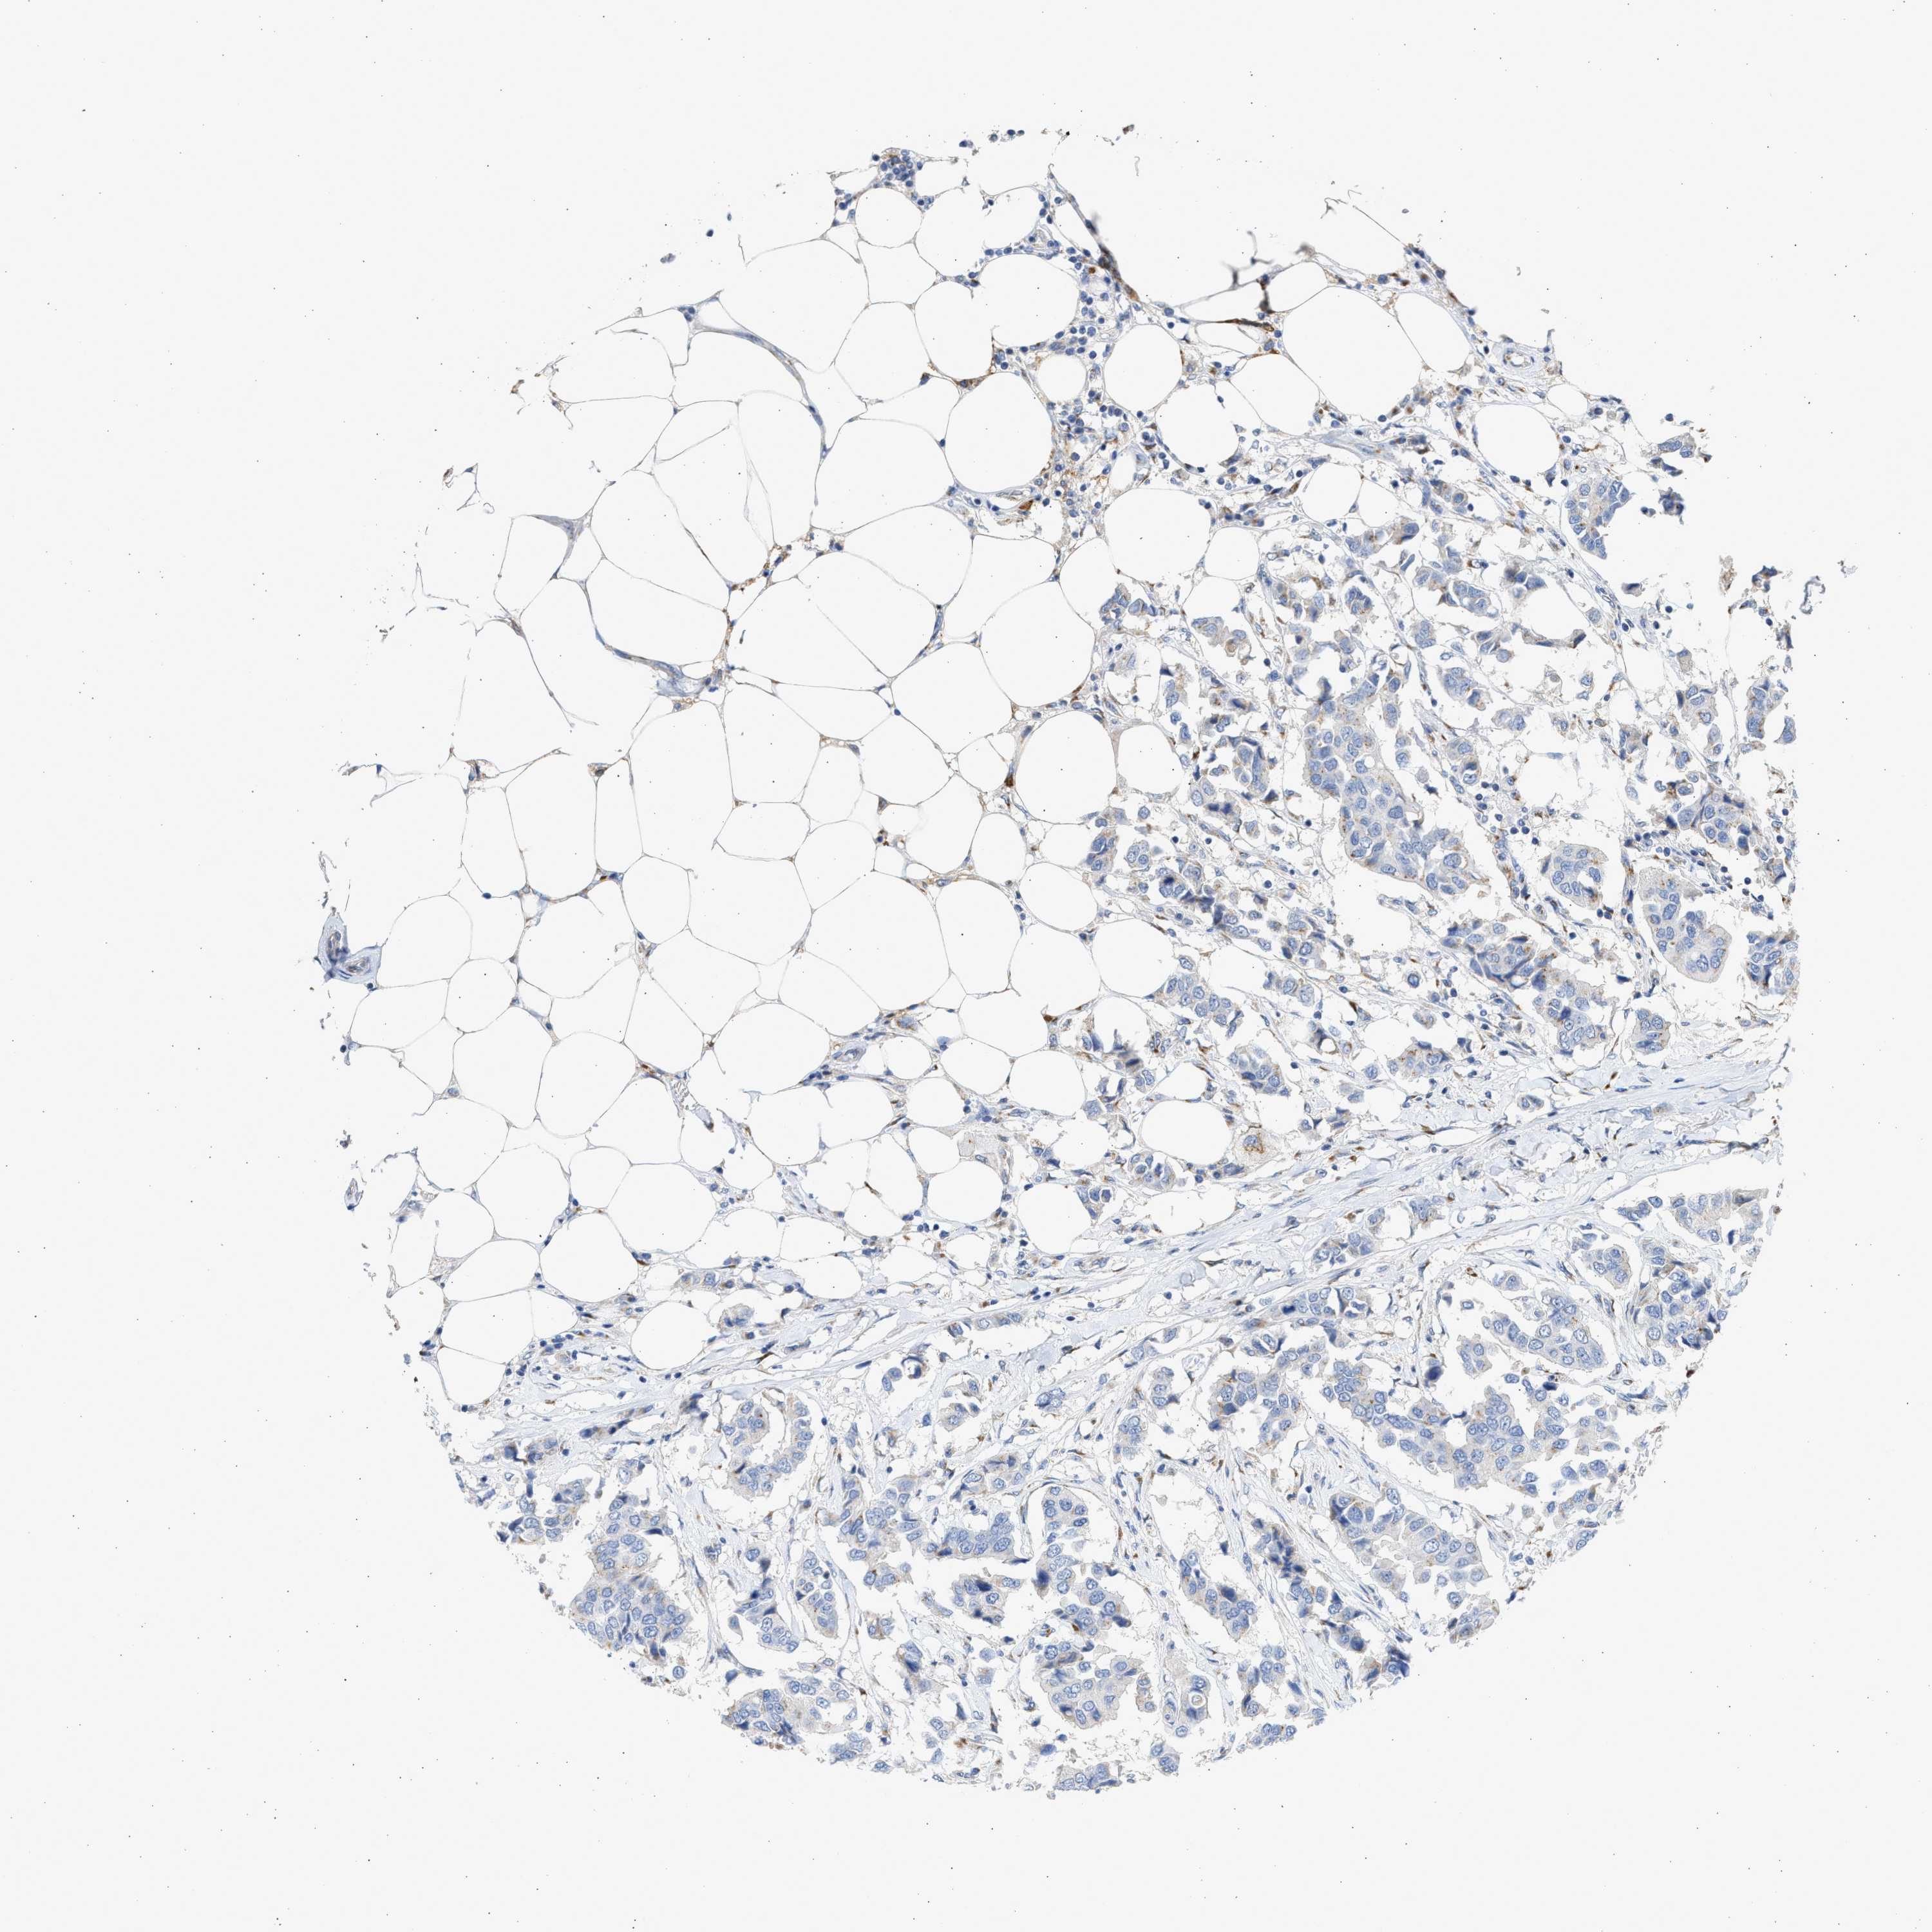

CANCER BREAST CANCER Show tissue menu

BRCA TCGA BRCA VALIDATION PROTEIN EXPRESSION